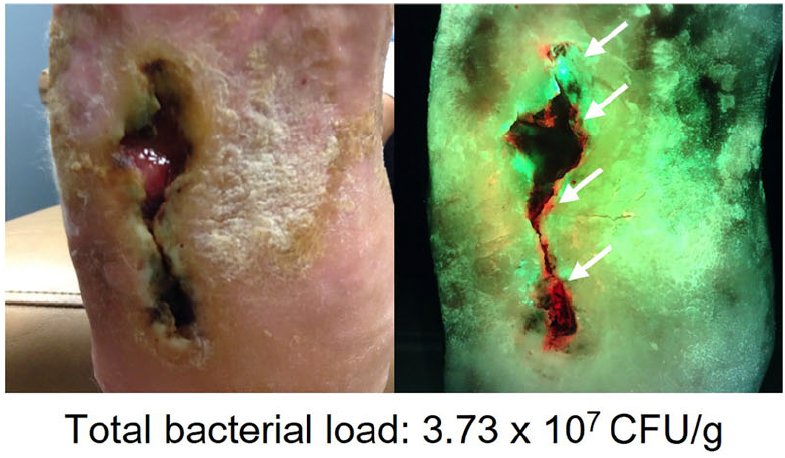

Unveiling the relationship between pain and bacterial load in venous ulcers with implications in targeted treatment

Oropallo A. et al. JVS-VL 2025

Diagnosis and treatment of the invasive extension of bacteria (cellulitis) from chronic wounds utilizing point-of-care fluorescence imaging

Andersen, A. et al. Int Wound J 2021

Real-time bacterial fluorescence imaging accurately identifies wounds with moderate-to-heavy bacterial burden

Serena, TE et al. J Wound Care 2019